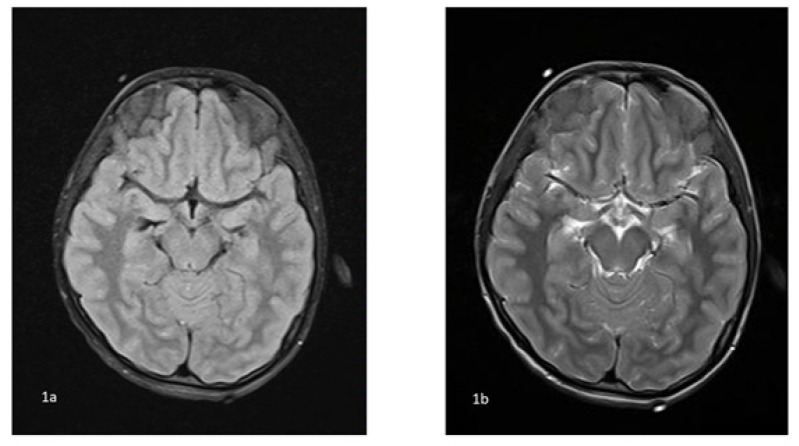

Results: There were 10 cases in the age range of 1-15 years. All the cases had elevated COVID-19 antibodies with history of contact 2-3 weeks prior except one who was positive for COVID-19 infection. Two cases presented with acute ascending paralysis suggestive of Guillain-Barre syndrome. Four cases presented with features of encephalopathy with clinical presentation fulfilling the criteria of Multisystem inflammatory syndrome in children. One case presented with fever and focal seizures with MRI showing sagittal sinus thrombosis, and one presented with fever and altered sensorium with MRI showing leukoencephalopathy. One child had cerebral mucormycosis without any evidence of immunosuppression. There was one child with features of encephalopathy with active COVID-19 infection.